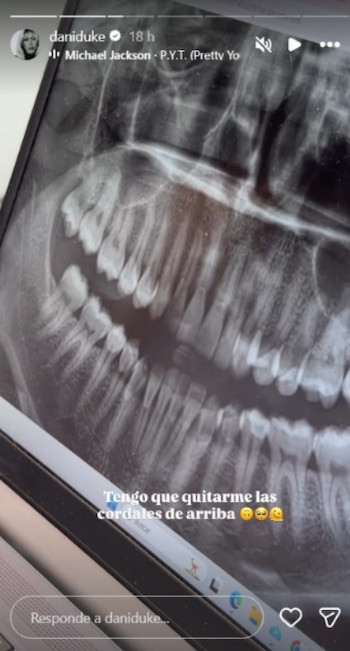

En sus historias, Duke explicó que la consulta odontológica comenzó como una revisión general tras varios días de malestar. La profesional que la atendió ordenó realizar radiografías, procedimiento tras el cual se determinó que sus muelas cordales superiores estaban generándole problemas y era necesario retirarlas cuanto antes.

“Tengo que quitarme las cordales de arriba”, relató la influenciadora, agregando que la recomendación surgió luego de conocer el resultado de los exámenes.

Las muelas cordales, conocidas popularmente como muelas del juicio, suelen requerir extracción cuando no disponen del espacio suficiente para salir correctamente en la boca, lo que puede dar lugar a dolor, inflamación, infecciones y daño en los dientes vecinos.

Además, su difícil acceso hace que la higiene en esa parte sea más compleja, aumentando el riesgo de caries y acumulación de placa, situación que la propia Dani Duke reconoció en su explicación a la audiencia.

Entre los motivos que justifican la intervención inmediata se encuentra la prevención de complicaciones, ya que “retirarlas a tiempo evita problemas mayores como quistes, enfermedad periodontal o emergencias por infecciones fuertes”, según detalló la creadora de contenido. Por la ubicación y el estado en que suelen aparecer estas muelas, la extracción preventiva permite mantener una salud bucal adecuada y reduce la posibilidad de emergencias odontológicas a futuro.